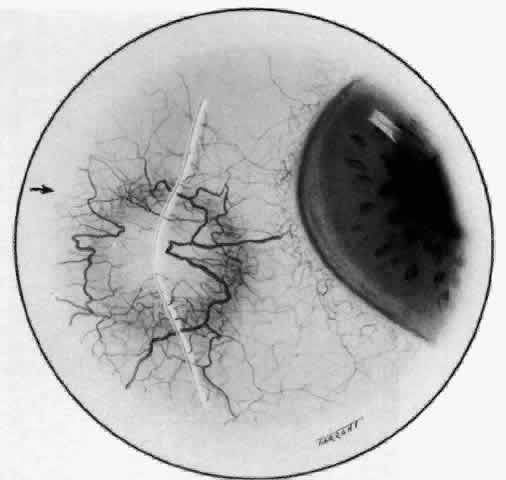

ARTERIAL PHASE Anterior Episcleral Arterial Circle The anterior ciliary arteries run radially toward the limbus within Tenon's capsule, giving few, if any, branches until they reach the anterior part of the globe. Their positions are very variable, and they do not always follow the rectus muscles. They bifurcate 2 to 5 mm behind the limbus, and each division runs forward and circumferentially to anastomose with a branch from an adjacent artery. This results in an anterior episcleral arterial circle (Figs. 3 through 5). The divisions of the anterior ciliary arteries are typically superficial at their origins but run deeper at their anastomoses. They occasionally dip too deep to be seen in fluorescein angiograms (Fig. 6).

From the anterior episcleral arterial circle, four distinct circulations are supplied: episcleral, anterior conjunctival, limbal, and iris. Episcleral Circulation Immediately after their origin by bifurcation of the anterior ciliary arteries, the contributions to the anterior episcleral circle divide again to give recurrent branches that run posteriorly and subdivide to form a netlike episcleral plexus (see Fig. 5; Fig.7). The variability of the positioning of the anterior ciliary arteries inevitably leaves large areas of episclera far from such an arterial supply (see Figs. 4, 6, and 7). These areas receive other posterior branches from the episcleral circle. Where the circle runs deep within the sclera, such branches appear as isolated perforating vessels (see Fig. 6). They fill very shortly after the episcleral circle, and they also divide repeatedly as they run posteriorly.